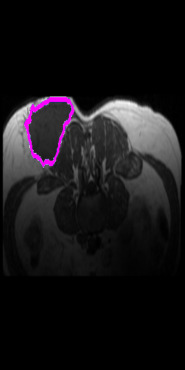

Radiomics uses quantitative medical imaging features to predict clinical outcomes. Currently, in a new clinical application, finding the optimal radiomics method out of the wide range of available options has to be done manually through a heuristic trial-and-error process. In this study we propose a framework for automatically optimizing the construction of radiomics workflows per application. To this end, we formulate radiomics as a modular workflow and include a large collection of common algorithms for each component. To optimize the workflow per application, we employ automated machine learning using a random search and ensembling. We evaluate our method in twelve different clinical applications, resulting in the following area under the curves: 1) liposarcoma (0.83); 2) desmoid-type fibromatosis (0.82); 3) primary liver tumors (0.80); 4) gastrointestinal stromal tumors (0.77); 5) colorectal liver metastases (0.61); 6) melanoma metastases (0.45); 7) hepatocellular carcinoma (0.75); 8) mesenteric fibrosis (0.80); 9) prostate cancer (0.72); 10) glioma (0.71); 11) Alzheimer's disease (0.87); and 12) head and neck cancer (0.84). We show that our framework has a competitive performance compared human experts, outperforms a radiomics baseline, and performs similar or superior to Bayesian optimization and more advanced ensemble approaches. Concluding, our method fully automatically optimizes the construction of radiomics workflows, thereby streamlining the search for radiomics biomarkers in new applications. To facilitate reproducibility and future research, we publicly release six datasets, the software implementation of our framework, and the code to reproduce this study.

翻译:放射科使用定量医学成像特征来预测临床结果。目前,在一个新的临床应用中,通过一个超常试验和高压过程,通过人工操作,从广泛的现有选项中找到最佳放射法。在本研究中,我们提议了一个框架,自动优化每个应用程序的放射工作流程的建设。为此,我们将放射作为模块工作流程,并包括每个部件的大量通用算法。为了优化每个应用程序的工作流程,我们使用随机搜索和聚合的自动机学习方法。我们用12种不同的临床应用来评估我们的方法,结果在曲线下应用的以下领域:1) 脂色瘤(0.83);2) 脱氧型纤维瘤(0.82);3 初级肝脏肿瘤(0.80);4 气肠肿瘤(0.77)、5 彩虹肝脏移植(0.61); 6 脑膜细胞变异常(0.45); 7) 肝细胞变异常(0.8) 脑纤维变异位(0.80); 9) 直径直线型癌症(0.74) 和头型癌症(0.77) 直径研究(10) 。